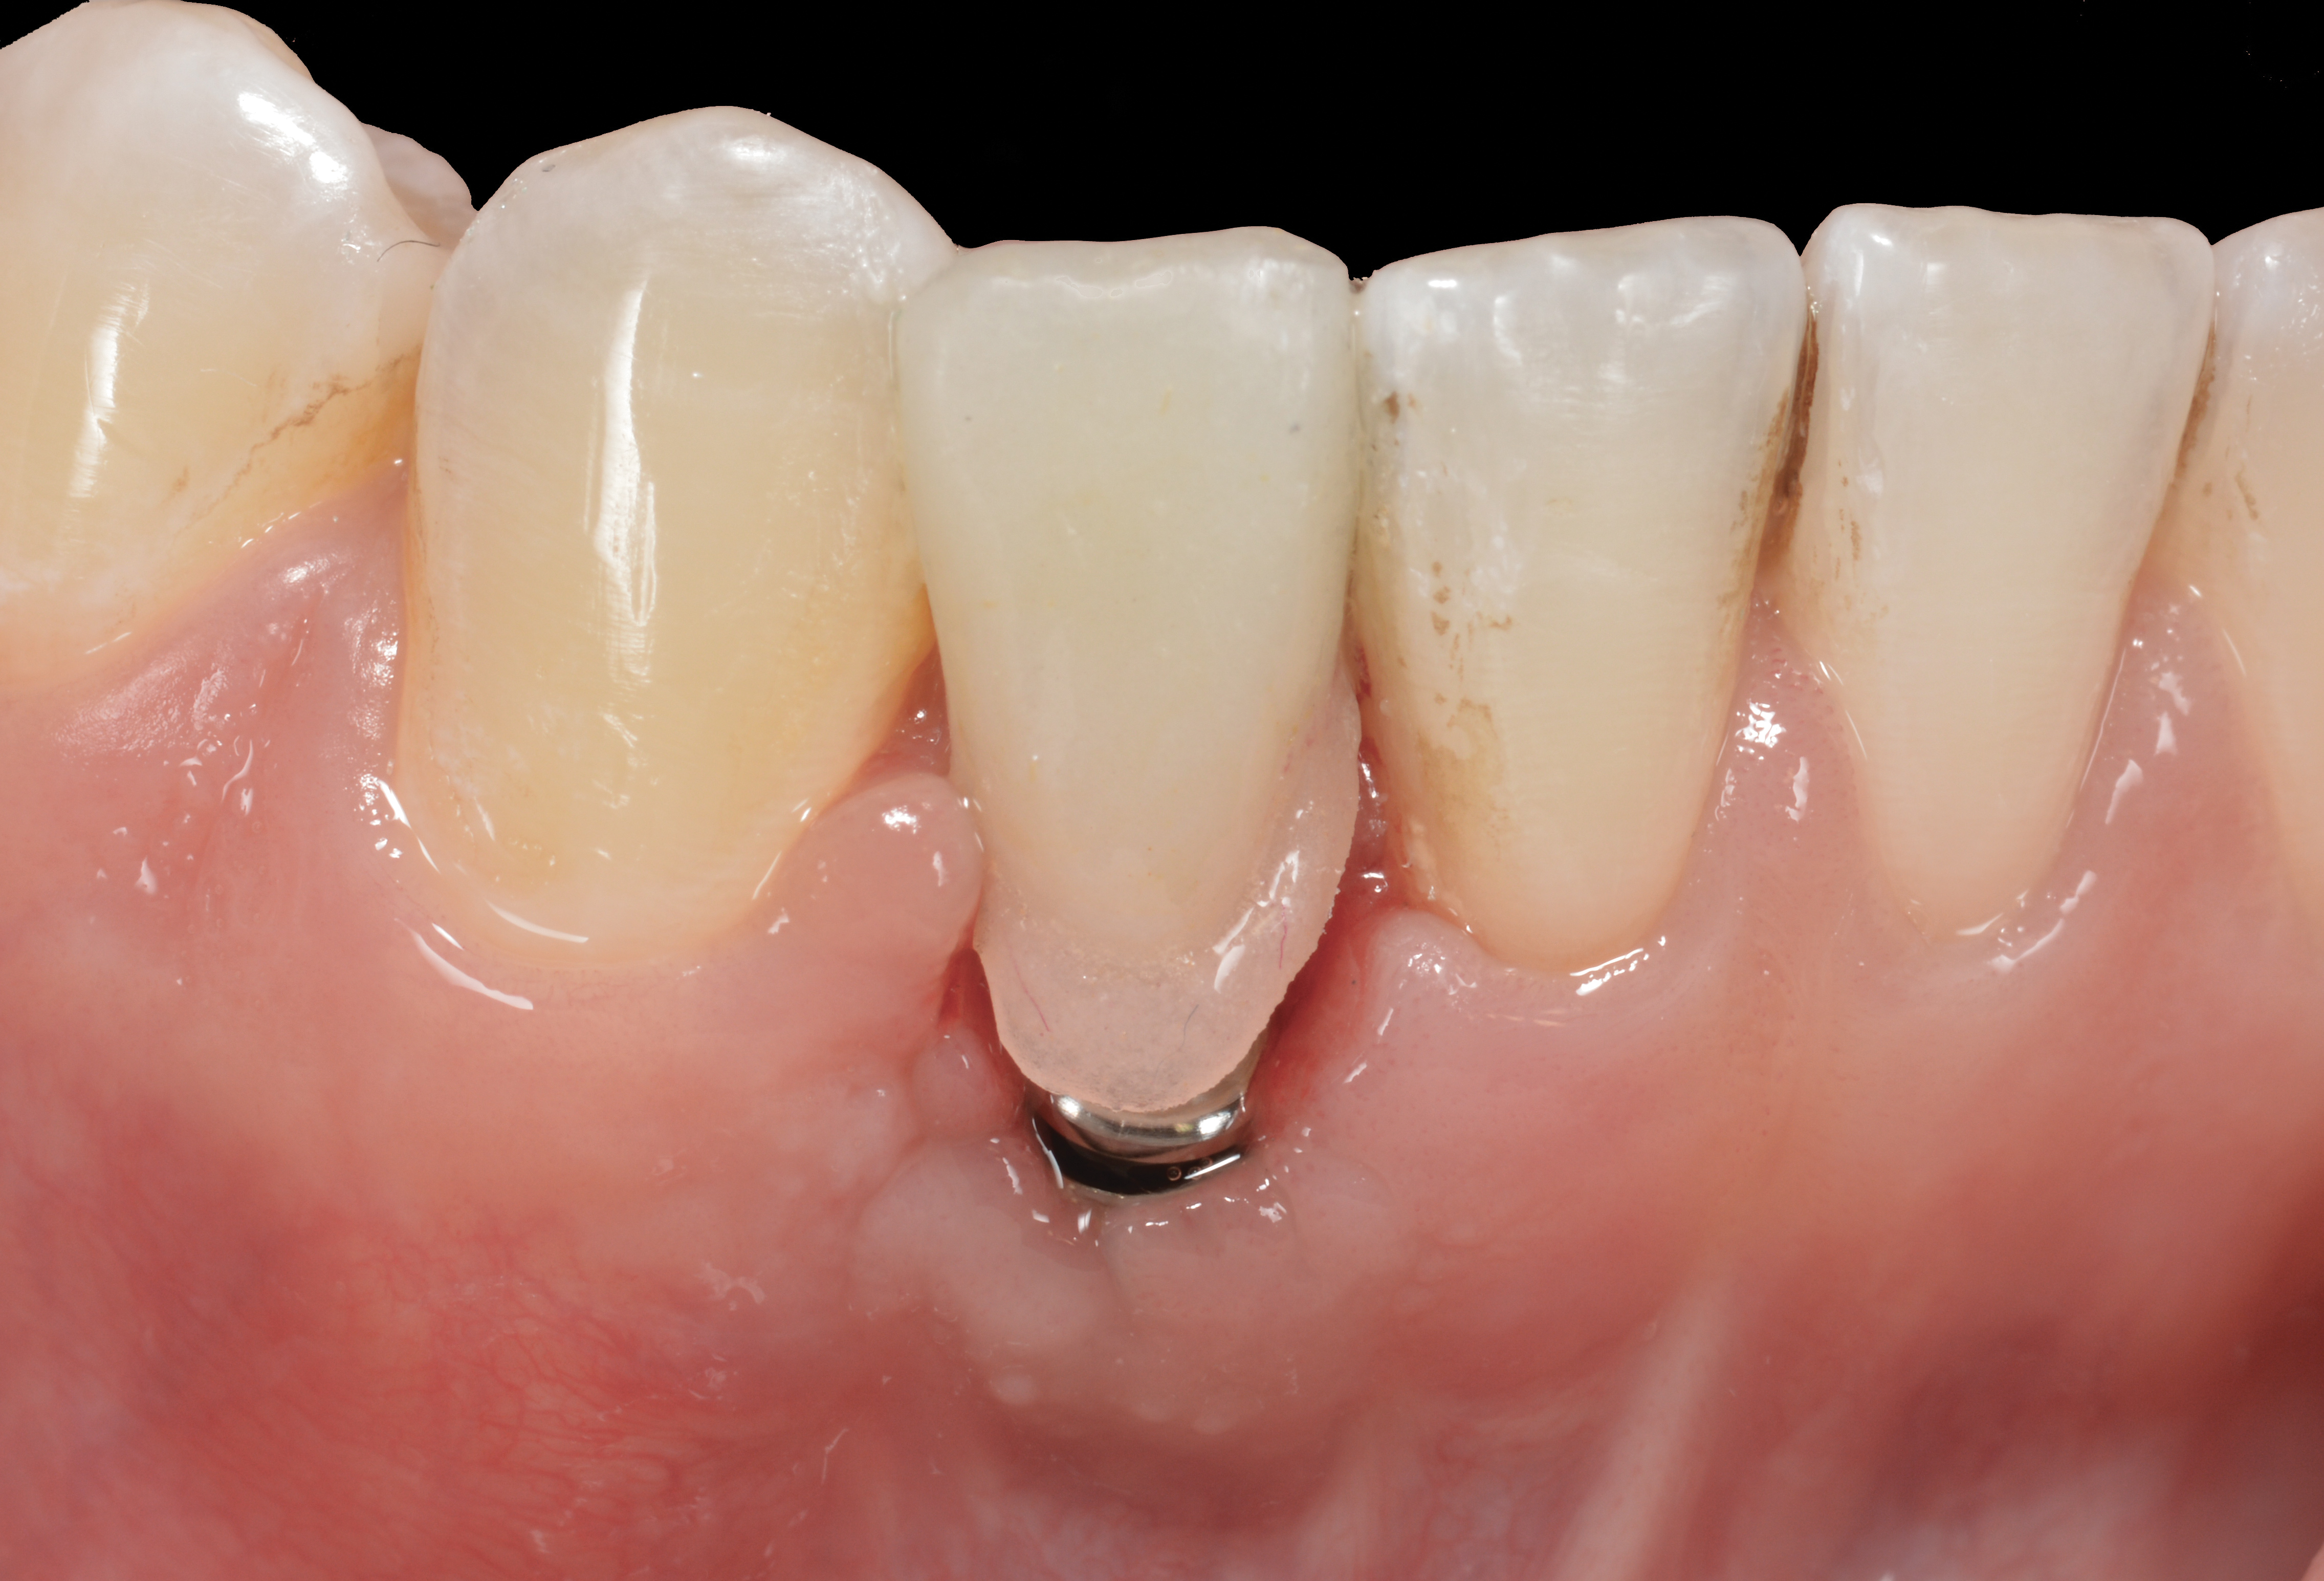

Problem: The implant is placed too facially, and there is significant labial gingival recession, contour change, and mucosal discoloration around the implant, abutment, and crown (Figure 3 and Figure 4). The implant attachment apparatus is intact and healthy, but the patient has a thin periodontal phenotype.

The following case report provides an example of this case scenario: A 28-year-old white female patient presented with her maxillary right lateral incisor significantly longer than the contralateral tooth following restoration of an existing crown that was 10 years old (Figure 3). The patient was dissatisfied with the esthetic appearance of the restoration due to the increased length, recession of the gingival tissues, and discoloration of the surrounding mucosa (Figure 4). Similar to case scenario No. 1, the first step in treatment was to decoronate the healthy implant by placing a flat surgical cover screw and employing a provisional resin-bonded-retained (RBR) prosthesis as a transitional fixed restoration (Figure 5 and Figure 6). The gingival augmentation in situ was allowed to take place for 2 to 3 weeks and was evaluated after that time (Figure 7).

Fig 3. A patient presented with a high smile line and midfacial recession of the maxillary right lateral incisor as evidenced by the increased tooth length compared with the contralateral lateral incisor.

Fig 4. Intraoral view of tooth No. 7 with the gingival zenith more apical than the adjacent central incisor and canine tooth.

Fig 5. A surgical cover screw was placed onto the implant in order to achieve gingival augmentation in situ prior to a secondary soft-tissue procedure.

Fig 6. A transitional resin-bonded-retained dental prosthesis was used to replace tooth No. 7.

Fig 7. The gingiva was allowed to grow over the cover screw for a 2- to 3-week period. The soft-tissue shape was still deficient and would require a secondary augmentation procedure.

Fig 8. A subepithelial connective tissue graft was placed.

Fig 9. After 3 months of healing, the implant was uncovered. A crestal incision was made with a palatal bias and rolled to the labial side to increase the soft tissue to the facial aspect.